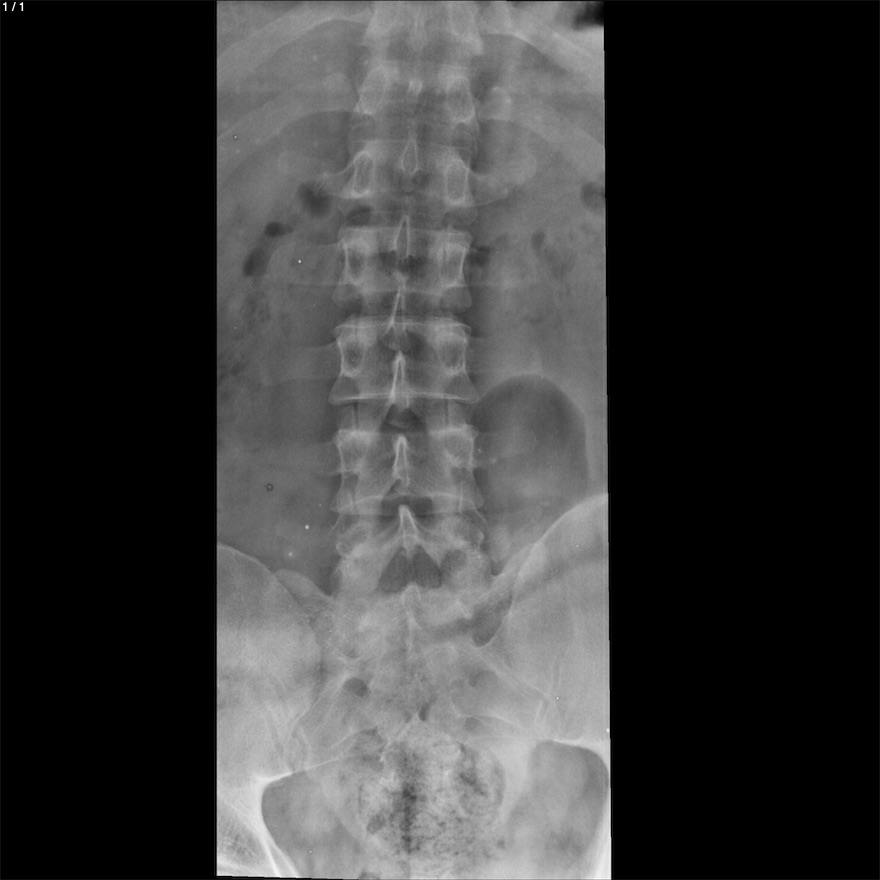

Charly Alexander Ruiz Cigarroa - Unnamed